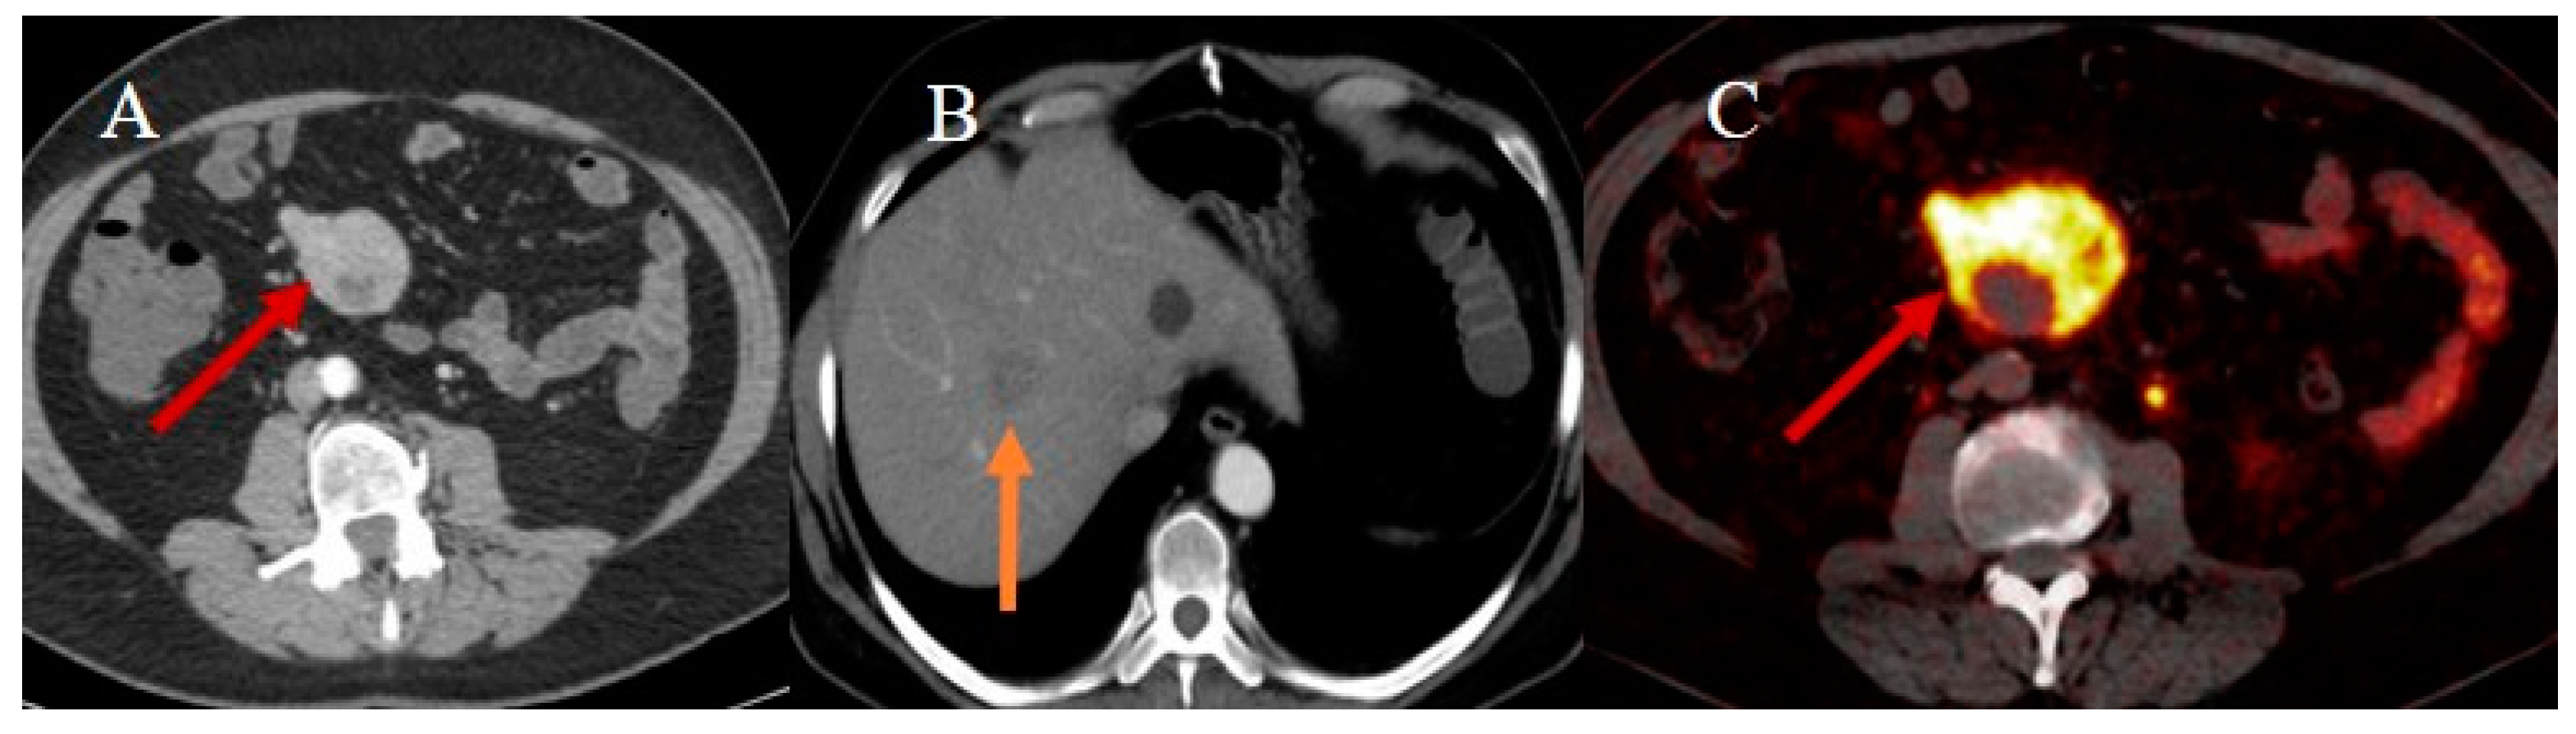

- Bonomi, A.; Romario, U.F.; Funicelli, L.; Conti, G.; Luc, M.R.; Ceci, F.; Pozzi, S.; Radice, D.; Fazio, N.; Bertani, E. Diagnosis and staging of small intestinal neuroendocrine tumors with CT enterography and PET with Gallium-68: Preoperative risk stratification protocol. Langenbecks Arch. Surg. 2024, 409, 63. [Google Scholar] [CrossRef]

| PET/CT | Staging and restaging of SBTs | 2-deoxy-2-18F-D-glucose (FDG) is the most commonly used tracer; 68-Gallium (68Ga)-DOTA peptide (DOTATATE, DOTATOC, and DOTANOC) PET/CT is used in small bowel NETs; full body scan acquisition | Ability to detect local and distant metastatic disease; 68-Gallium (68Ga)-DOTA peptide has higher sensitivity and specificity for small bowel; NETs tumor localization, staging, and receptor status assessment; 68-Gallium DOTATATE PET/CT is accurate for detecting initial or recurrent NETs in patients with carcinoid-like symptoms and negative anatomical imaging | PET/CT can produce false positives in patients with inflammation or infection; PET/CT has less spatial resolution than CT and MRI; PET and CT images can be misregistered due to the small bowel’s mobility |